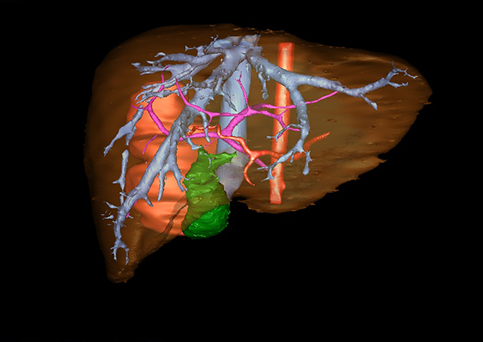

目前常用的检查方法有B超检查、CT、MRI、血管造影等。与其它的腹部肿块的诊断不同,对于小儿肝母细胞瘤血管造影具有重要的意义,可以作为手术前介入治疗的手段,也可为手术提供非常有效的影像学指导,但技术要求高,操作较复杂,且给患儿带来一定的痛苦。近年借助计算机辅助手术系统进行CT原始影像三维重建、手术规划和计算机虚拟手术技术,为精准肝脏手术提供了极为有效的技术支持。

近年来由于数字医学的发展,基于可视化三维重建技术的计算机辅助手术系统极大推进了小儿肝脏肿瘤的精准手术的进步。可以立体透视肝脏解剖、精确掌握肝段的边界、精确测算肝段乃至任意血管所支配的功能体积、准确定位病灶及其与邻近血管的解剖关系,最终对不同手术方案进行比较、筛选和优化。因此,计算机辅助手术规划系统是实现精准肝切除的有力辅助工具,是未来数字外科、精准外科等21世纪外科新理念的重要技术支撑。

计算机辅助手术规划系统具有良好的操作可行性、计算准确性和三维显示效果,可半透明、交互式显示真实的肝内立体解剖关系和空间管道变异,准确计算肝内管道的直径、走行角度,两点间的垂直距离,和任意血管的支配或引流范围等传统二维影像无法获取的信息,有助于实施个体化手术,提高了手术的确定性、预见性和可控性。计算机辅助手术规划系统可直观显示预留肝脏的结构和功能,并可通过虚拟切割功能辅助术者对手术方案进行蹄选和优化,系统评估手术风险和制定对策,改变了部分二维规划的术式和切除范围,使部分二维规划认为不能切除的患者成功手术,提高了手术的根治性、安全性和病变的可切除性,更加符合精准肝脏外科的术前规划要求。详见第11章。

随着计算机技术及影像检查技术的不断发展,以精确的术前影像学和功能评估、精细的手术操作为核心的精准肝切除技术日益受到重视。基于数字医学的计算机辅助手术技术(computer-assisted surgery,CAS)则是实现肝脏精准手术操作的基础。计算机辅助手术系统(CAS)可将术前二维(two dimensional,2D)的CT/MRI影像数据进行三维(three dimensional,3D)重建,建立个体化的肝脏三维解剖模型,清晰显示肝脏内脉管系统的走行及解剖关系,还原病灶与其周围脉管结构的立体解剖构象,准确地对病变进行定位、定性和评估,制定合理、定量的手术方案,实施个体化的肝脏血管取舍分配方案及实施精准肝脏手术。一般认为CAS包括:创建虚拟的患者的图像;患者图像的分析与深度处理;诊断、手术前规划、手术步骤的模拟;术中实时导航。应用本技术后,由于可以更清晰地看出肿瘤的界限,特别是根据肝血管的显影,判断出肿瘤与门静脉及肝静脉的关系以在手术前较准确地估计出手术成功切除的可行性。以往部分根据普通强化CT判断无法手术的病例而被评估为可以成功切除并手术成功。